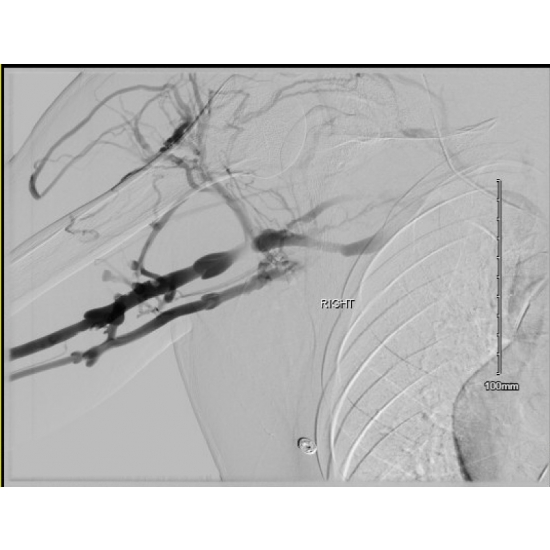

Peri-operative right upper extremity venogram demonstrated a complete occlusion of the right brachial, axillary, & subclavian veins. Large collateral from brachial to basilic vein, which appeared to drain the majority of the right upper extremity. Patent superior vena cava & right internal jugular.

BRACHIAL AND AXILLARY VEINS

Pre-Angio: NOTE COLLATERAL FLOW VIA PERFORATING VEINS FROM DEEP (BRACHIAL, AXILLARY, SUBCLAVIAN) TO SUPERFICIAL SYSTEM (IJ)